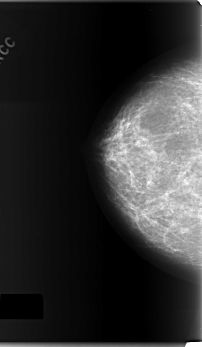

C_0165_1.LEFT_MLO

LEFT_CC LINES 5992 PIXELS_PER_LINE 3472 BITS_PER_PIXEL 12 RESOLUTION 50 OVERLAY

LEFT_MLO LINES 6016 PIXELS_PER_LINE 3504 BITS_PER_PIXEL 12 RESOLUTION 50 OVERLAY